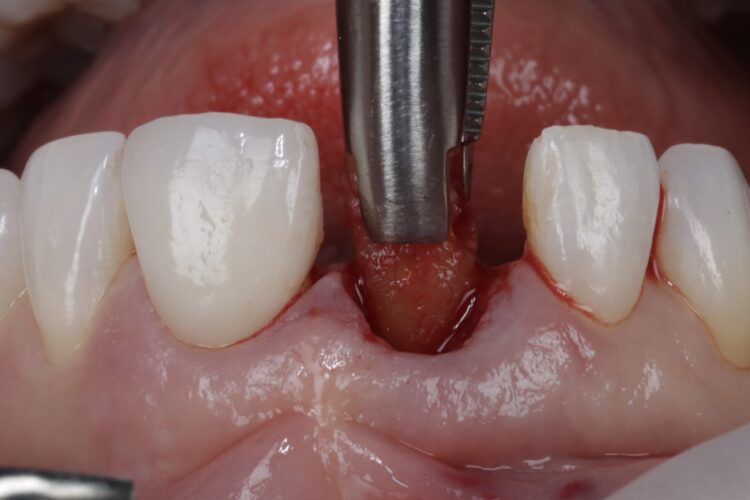

The implant was placed in close contact with the palatal bone, 1mm below the buccal bone height. A temporary cylinder abutment was connected, with flowable composite placed to attach the temporary restoration. The composite resin was used to create the optimal emergence profile ensuring a highly polished restoration in the transition zone.

Soft tissue regeneration

A free gingival graft was harvested from the palate, allowing enough tissue to reach between the base of each papilla and this was de-epithelialised to obtain the connective tissue. A thickness of 1mm is adequate, but in this instance, it was made intentionally thicker at the disto-buccal aspect to help plump up the papilla where bone loss was greater. The connective graft tissue was stabilised with three resorbable sutures placed, positioning the connective tissue graft 1mm below the free gingival margin.